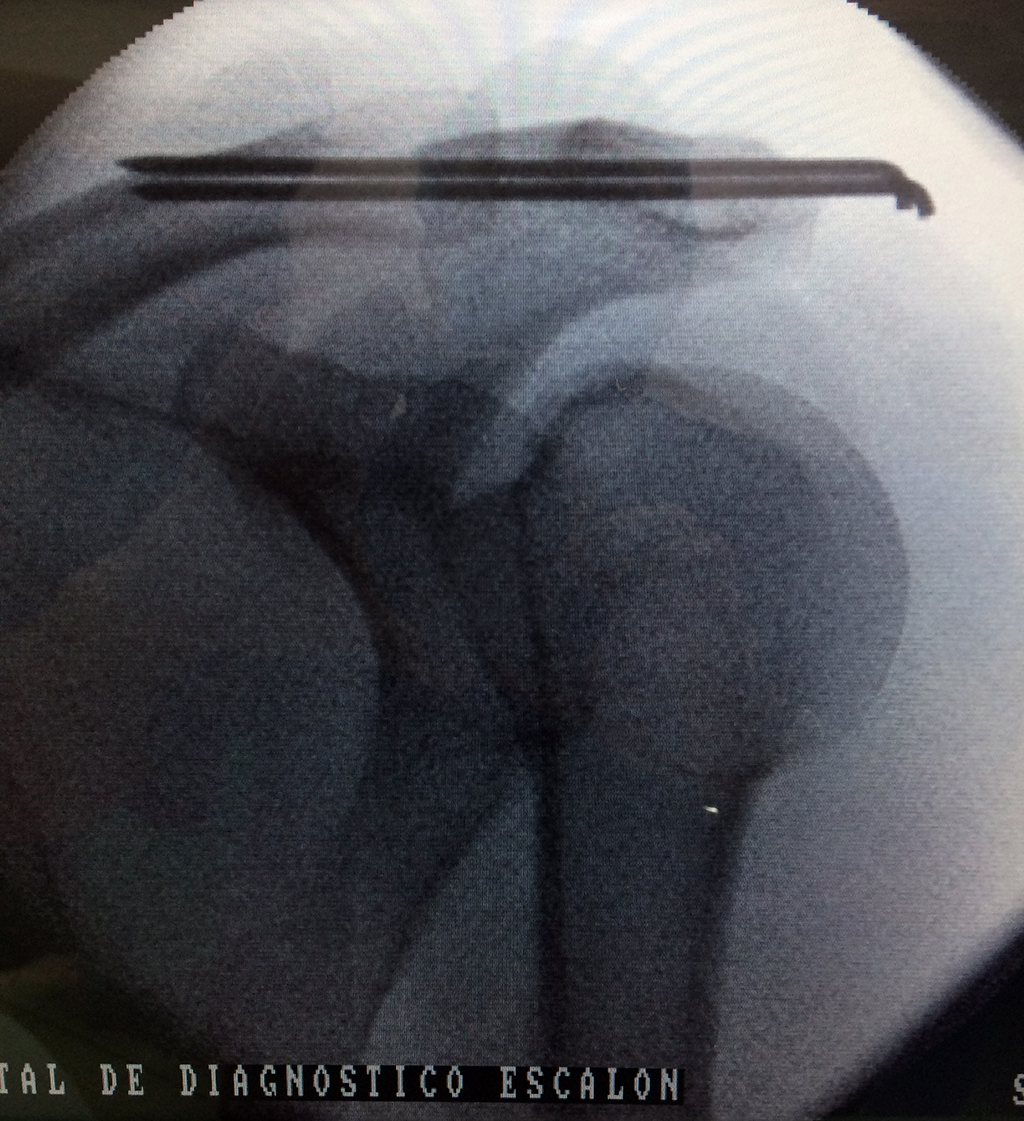

Fémur - Clavícula

La clavícula es un hueso largo, con forma de "S" itálica, situado en la parte anterosuperior del tórax. Junto con la escápula forman la cintura escapular. Se puede palpar por toda su longitud y se extiende del esternón al acromion de la escápula, siguiendo una dirección oblicua lateral y posterior.